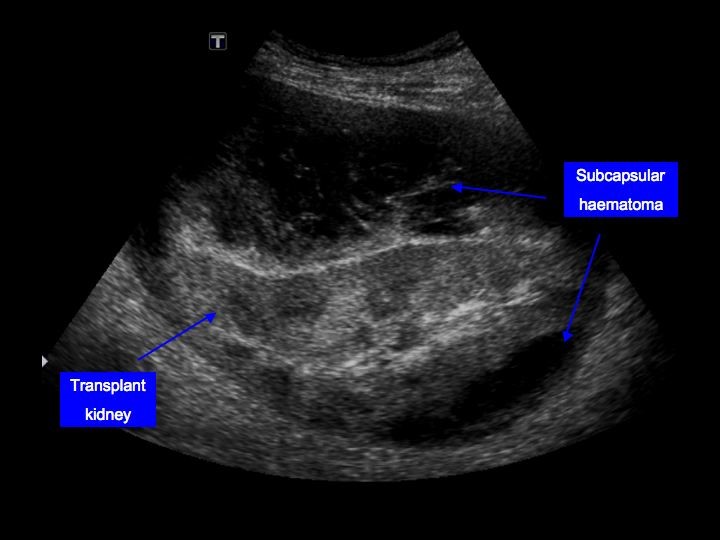

🚩Underneath the renal capsule ➡️ pressure tamponade & pain

9/ Chronic hypertension due to the "Page kidney"

Pressure-induced ischemia from a large subcapsular hematoma → activation of RAS→ HTN